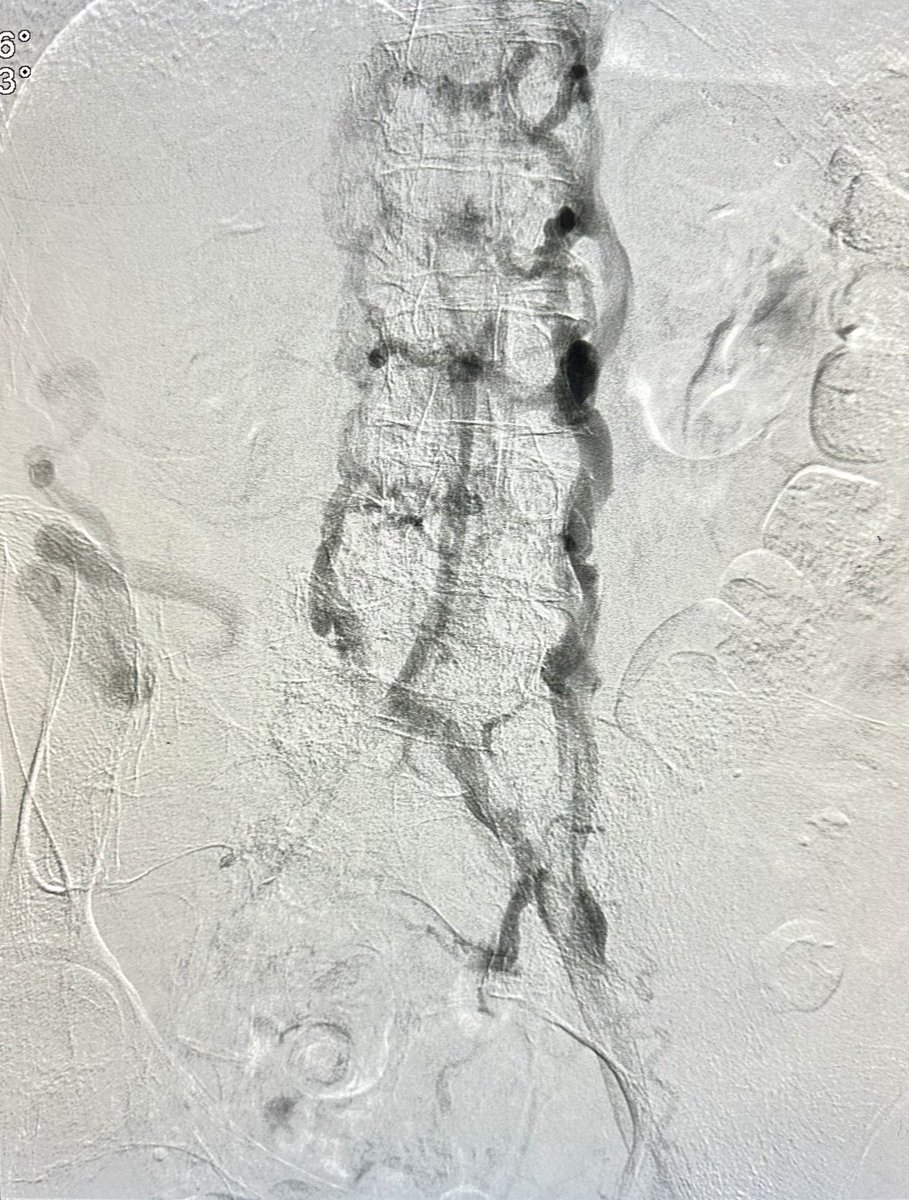

Pt with h/o LLE DVT rxed with surgical thrombectomy remotely, with B/L LE edema and ulcers. Had CTO of infrarenal IVC and bilateral iliac veins, treated with IVUS venoplasty, double barrel stenting of IVC to bilateral EIV and RCFV @OEISociety @VenousForum @VIVAPhysicians

dr_ashishg's tweet image. Pt with h/o LLE DVT rxed with surgical thrombectomy remotely, with B/L LE edema and ulcers. Had CTO of infrarenal IVC and bilateral iliac veins, treated with IVUS venoplasty, double barrel stenting of IVC to bilateral EIV and RCFV @OEISociety @VenousForum @VIVAPhysicians